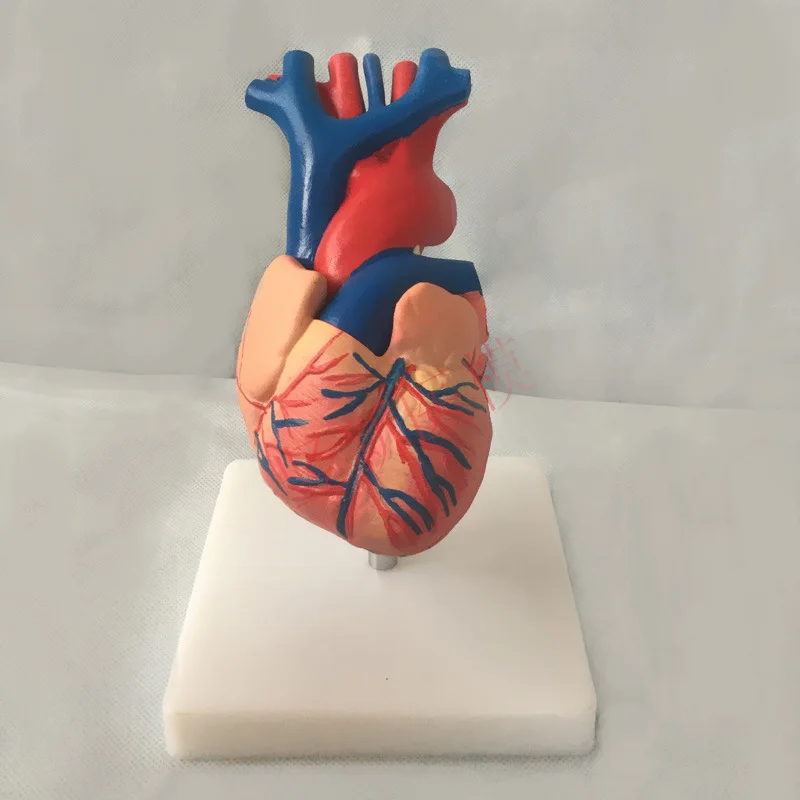

Фотографии и 3D-модели анатомии сердца человека